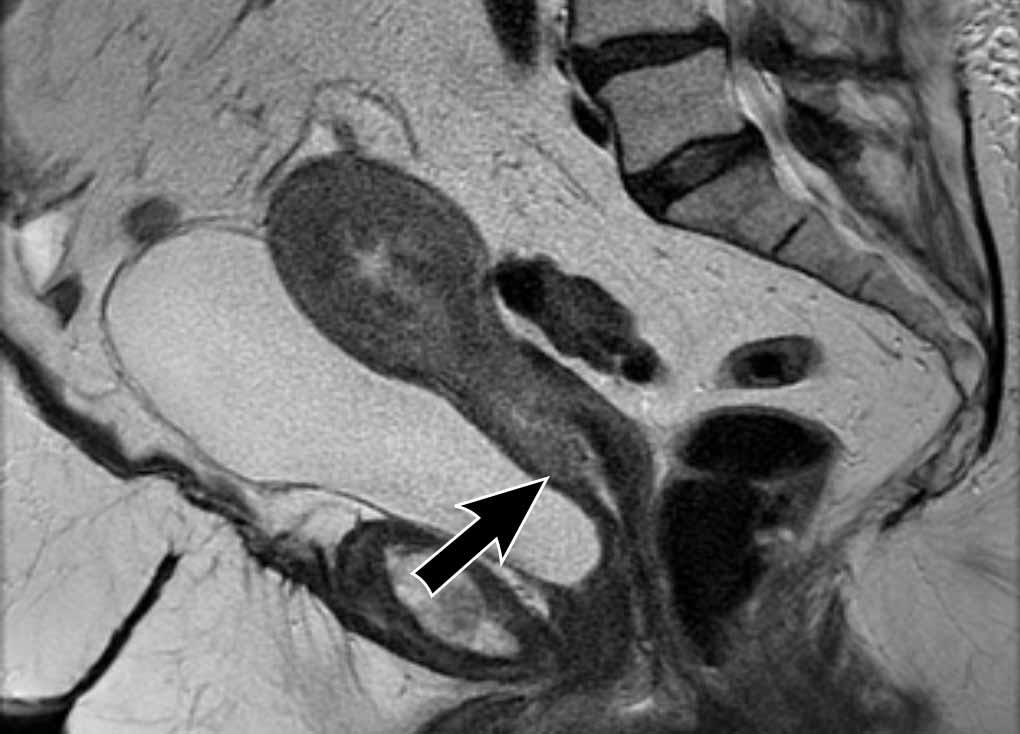

Xâm lấn mô đệm cổ tử cung

Xâm lấn mô đệm cổ tử cung có thể được phát hiện dưới dạng sự lan rộng của tín hiệu khối u kèm theo sự gián đoạn tín hiệu giảm bình thường của mô đệm cổ tử cung trên chuỗi xung T2W.

Nó cũng có thể được nhận diện dưới dạng sự gián đoạn ngấm thuốc bình thường của mô đệm cổ tử cung trên hình ảnh sau tiêm thuốc tương phản từ (CE), hoặc dưới dạng sự lan rộng của tín hiệu khối u cao trên DWI với giá trị b cao.

Hình ảnh

Có một khối u nội mạc tử cung xâm lấn mô đệm cổ tử cung ở phía trước.

Có sự lan rộng của tín hiệu trung gian của khối u làm gián đoạn tín hiệu giảm bình thường của cổ tử cung (mũi tên).